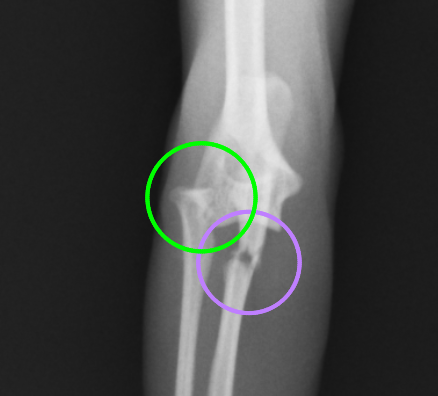

正面から撮影したX線の拡大です。紫が尺骨の骨折で、緑が、脱臼した橈骨になります。